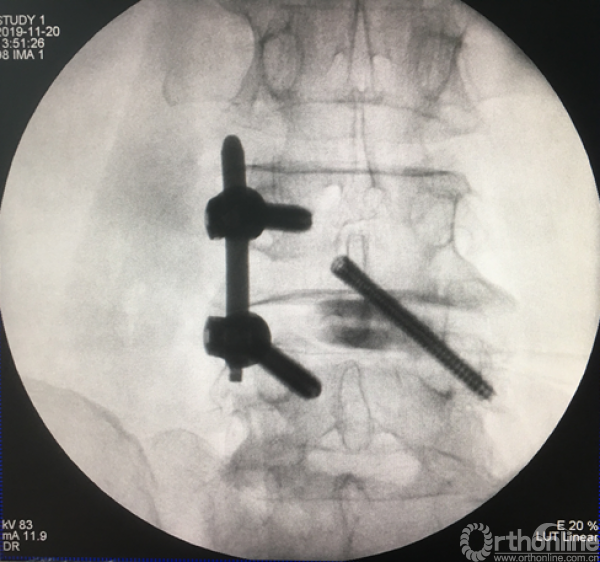

正侧位透视确定责任节段

正侧位透视观察滑脱是否复位、融合器及植骨的位置

术后正、侧位片